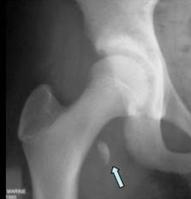

DESPRINDEREA NUCLEULUI SECUNDAR DE CALCIFICARE A TROHANTERULUI MIC

Traumatism la o gimnasta de 13 ani

Desprinderea nucleului de osificare secundar

al trohanterului mic pe care se insera tendonul

psoasului iliac

Confirmare radiologica